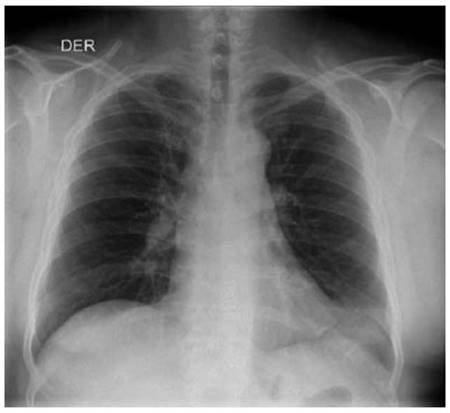

Al examen físico se observaba ictericia generalizada y ascitis grado 2 con signos vitales dentro de límites normales. En paraclínicos de ingreso se observaba con leucocitosis asociado a neutrofilia, anemia de volúmenes normales, trombocitopenia y un perfil de función hepática con elevación de transaminasas, un Factor R de 1.9 (Patrón colestásico); Se amplían estudios de etiología infecciosa con virus hepatotropos negativo, estudio liquido peritoneal negativo para peritonitis bacteriana espontánea, uroanálisis sugestivo de infección (Ver Tabla 1) y radiografía de tórax dentro de límites normales (Ver Figura 1). Debido a lo anterior se inició manejo para encefalopatía con rifaximina y lactulosa, con indicación de manejo adicional de ácido ursodesoxicolico y cubrimiento antibiótico dando continuidad con piperacilina/Tazobactam dosis de 4.5 gramos intravenoso cada 6 horas. Ante deterioro clínico de paciente con aumento de encefalopatía y persistencia de fiebre, alteración síntesis hepática (INR 2,5), progresión de anemia y trombocitopenia, se realiza toma de hemocultivos y estudio de líquido cefalorraquídeo con líquido dentro de límites normales. Se amplían estudios por nexo de procedencia del paciente de zona endémica selvática con gota gruesa seriada y antígenos febriles los cuales son negativos; se inicia cubrimiento Ceftriaxona 2 gramos/día intravenoso y Doxiciclina 100 mg vía oral cada 12 horas en día 2 de hospitalización.

Figura 1: Radiografía de tórax ingreso: Opacidad triangular en la língula, pudiendo corresponder a atelectasia. No se observan otras alteraciones en la transparencia pleuropulmonar. Ángulos costofrénicos libres, no hay signos derrame pleural.